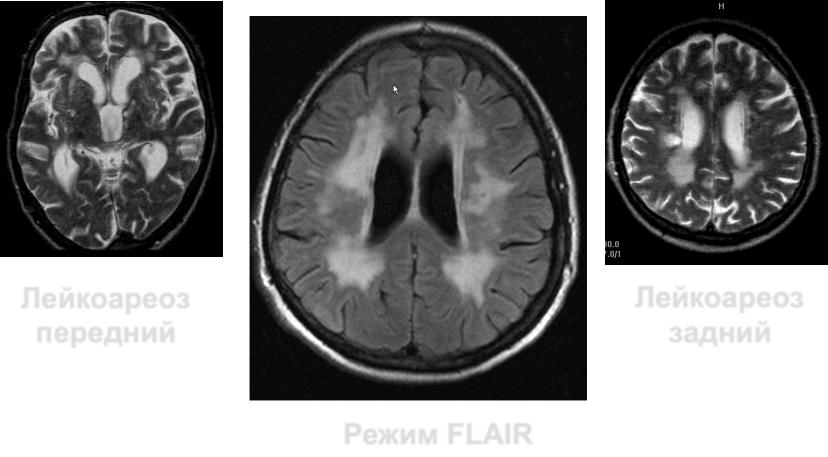

Термин лейкоареоз (от греч. leuko- белый и araiosis- разрежение) впервые был введен V.

Hachinski в 1987 году

Лейкоареоз

передний

задний

Режим FLAIR